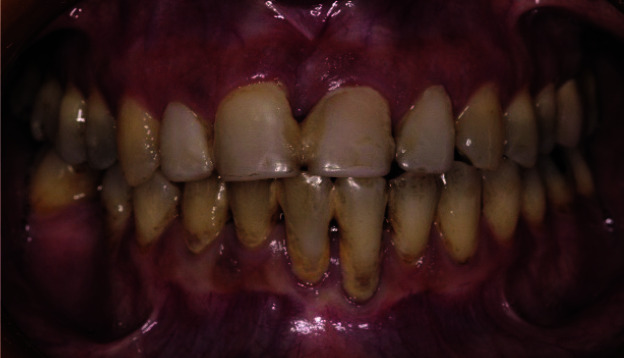

This case report exhibits a heavy smoker female patient with a localized stage III periodontitis who has been under the smoking cessation program during the pre-surgical period, followed by a strict maintenance program for the past twelve years, after being treated with guided tissue regeneration techniques and restored with zirconia prosthetic crowns. A 50-year-old, heavy smoker (> 40 cigarettes per day), systemically healthy female patient presented complaining of mobility and pain in the upper right central incisor, which was temporarily splinted to the left central incisor using resin composite. After clinical and radiographic examination, significant damage of the attachment apparatus, deep periodontal lesions extending the middle portion of the root, and severe infrabony defect were noted. Following the initial hygienic phase, a guided tissue regeneration surgery using xenograft bone substitute covered by a resorbable collagen membrane was performed. After six months of healing, four zirconia crowns were cemented on the central and lateral incisors based on patient esthetic compliance. During the 12-year follow-up period, neither residual pockets nor gingival recession were observed, and perfect marginal bone stability, and esthetic and functional results were noted. This case shows the predictability of a conservative surgical technique, the guided tissue regeneration, based on appropriate treatment planning and a strict maintenance program. It also demonstrates the importance of at least a 6-month healing period after such surgeries, allowing complete tissue maturation and a re-establishment of the supra osseous gingival tissues in order to locate the prosthetic margins without interfering with the soft tissues integrity.